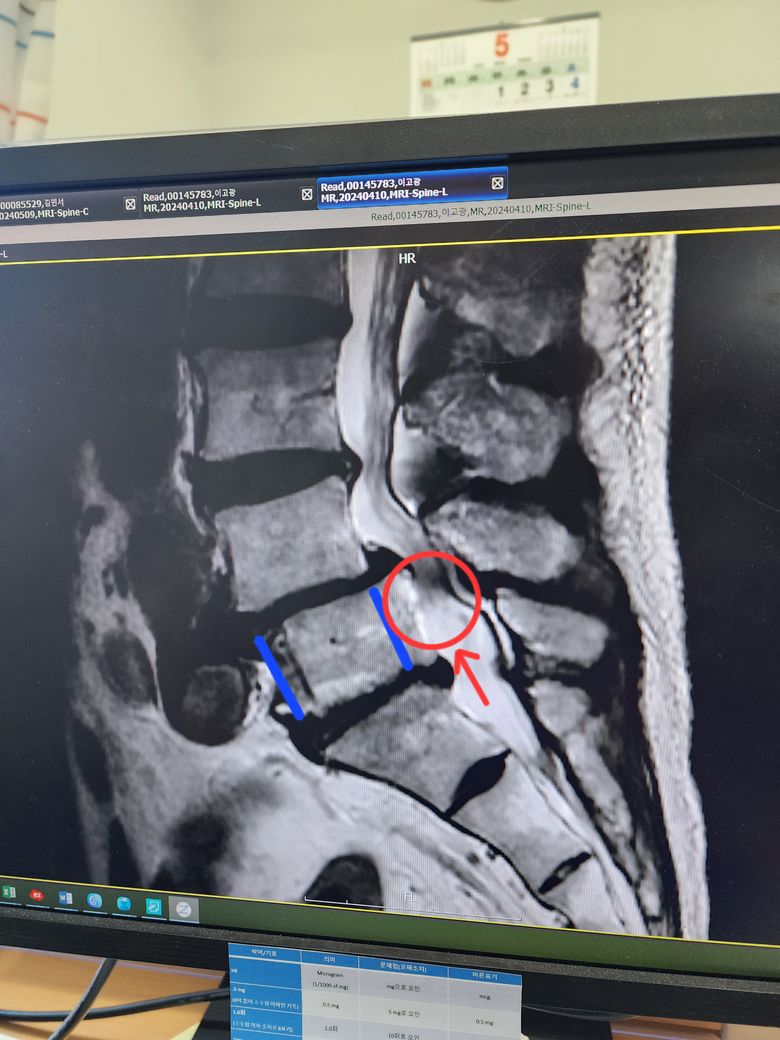

80대 노부 께서 다리가 힘이 없다고 해서 등쪽 사진을 찍어보니 사진처럼 척추 5번이 등쪽으로 밀려 있어 신경을 누른다고 하는데요. 나이가 있어 수술을 어렵다고 하는데 다른 추나요법이나 한방치료가 가능한지 궁금합니다